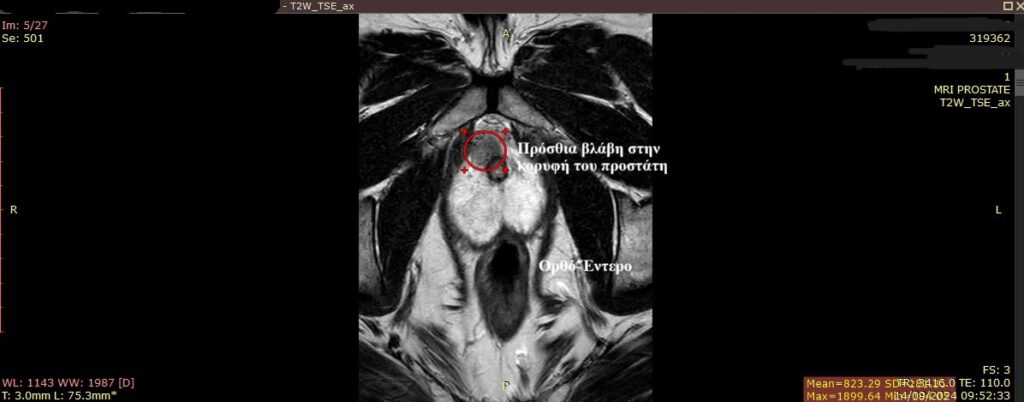

Πώς βοηθάει η πολυπαραμετρική μαγνητική στη διάγνωση του καρκίνου του προστάτη και στη βιοψία; (Βλ. Εικόνα 1)

Εικόνα 1: Σχεδιασμός του προστάτη (κόκκινο σχεδιάγραμμα) και σχεδιασμός της βλάβης (μπλε σχεδιάγραμμα).Με τον τρόπο αυτό σχεδιάζεται η βλάβη και ο ουρολόγος εν συνεχεία με την Fusion βιοψία προστάτη λαμβάνει στοχευμένες βιοψίες (Εικόνα από την συλλογή της Medcom).

Εικόνα 3: Χαρακτηριστική πρόσθια βλάβη στην κορυφή του προστάτη, μια δύσκολη ανατομική περιοχή που δεν είναι προσβάσιμη εύκολα από το έντερο με την διορθική βιοψία ενώ με την διαπερινεϊκή είναι εφικτό να γίνει η λήψη δείγματος.